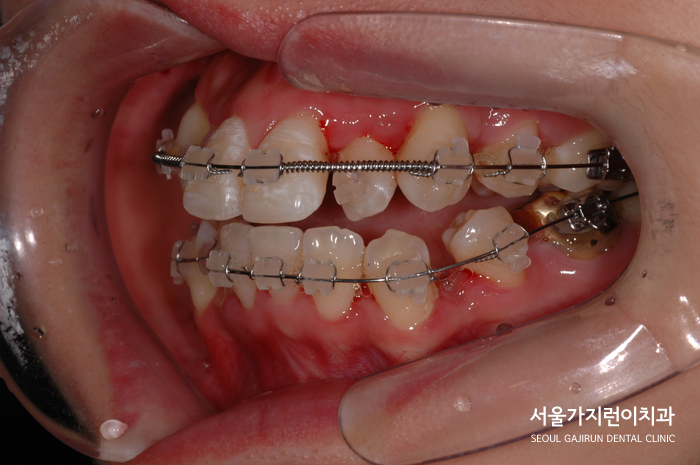

그래서 환자분의 경우 악궁이 좁아보이는 것을 확인해 발치를 진행해 공간을 확보하고 악궁을 넓히면서 자연스러운 아치 모양이 되도록 교정치료를 진행했습니다. 발치 교정을 진행했을 때는 어금니가 앞으로 끌려오지 못하도록 구개유지장치를 사용했는데요. (TPA), 발치 공간의 경우 앞니 쪽에서 제대로 닫게 하고 안정적인 교정결과를 위해 수술하지 않고도 치아이동을 이끌어냈습니다.